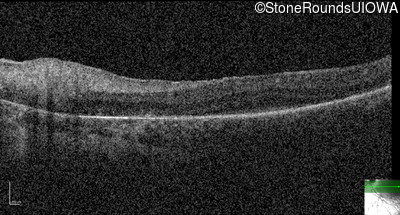

Optical Coherence Tomography - Right -

No Light Perception

Optical Coherence Tomography - Left -